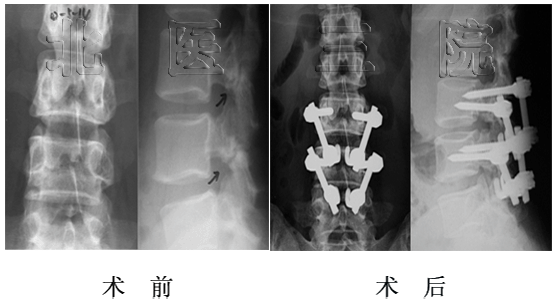

女性,17岁,胸腰段结核性后凸,术前后凸角度130o,经后路矫形术后仅剩37o,矫正率71.5%

男性,48岁,脊柱后凸畸形强直性脊柱炎,术前后凸角度115o,经后路矫形术后仅剩20o,矫正率82.6 %